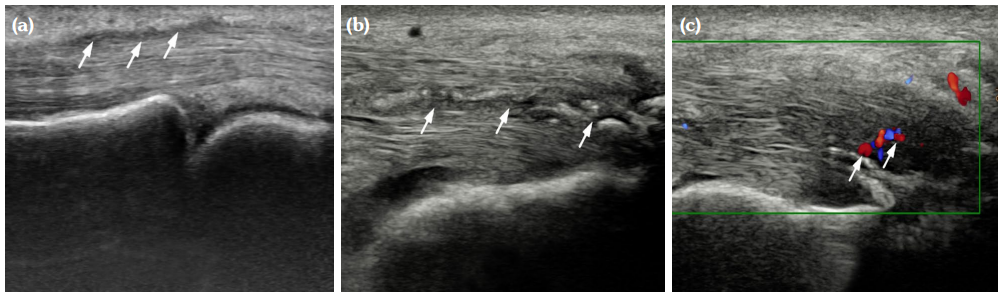

The degree of BE and synovial hyperplasia in SNRA or SPRA is more serious, and the blood flow signal is more abundant. However, the degree of synovial hyperplasia in osteoarthritis was mild, and no obvious blood flow signal was detected (Figures 1, 2, 3 and 4). Magnetic resonance imaging (MRI) studies of SPRA also showed serious BE (Figure 5).

Difference in ultrasound findings among SNRA, SPRA and non-RA groups

Among SNRA, SPRA and non-RA, there was no significant difference in the grades of SH, PD, BE, nor the number of cases of tendinitis and tenosynovitis between the SNRA group and the SPRA group (p>0.05) (Table 3). There were, however, statistically significant differences in the number of cases of SH1, SH3, PD and BE grades between the SNRA and non-RA groups (p<0.001). There was no significant difference in the number of cases of SH2, PD2, tendinitis or tenosynovitis between the SNRA and non-RA groups (p>0.05) (Table 4).